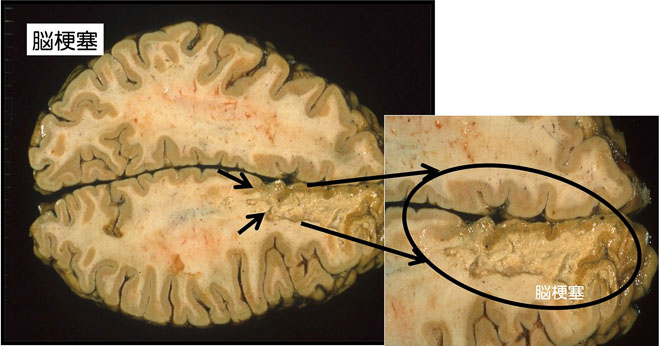

脳動脈が詰まると脳組織が壊死し、脳梗塞(図17)になります。

図17 脳梗塞 壊死を起こした大脳が融けたように見えるので脳軟化ともいう